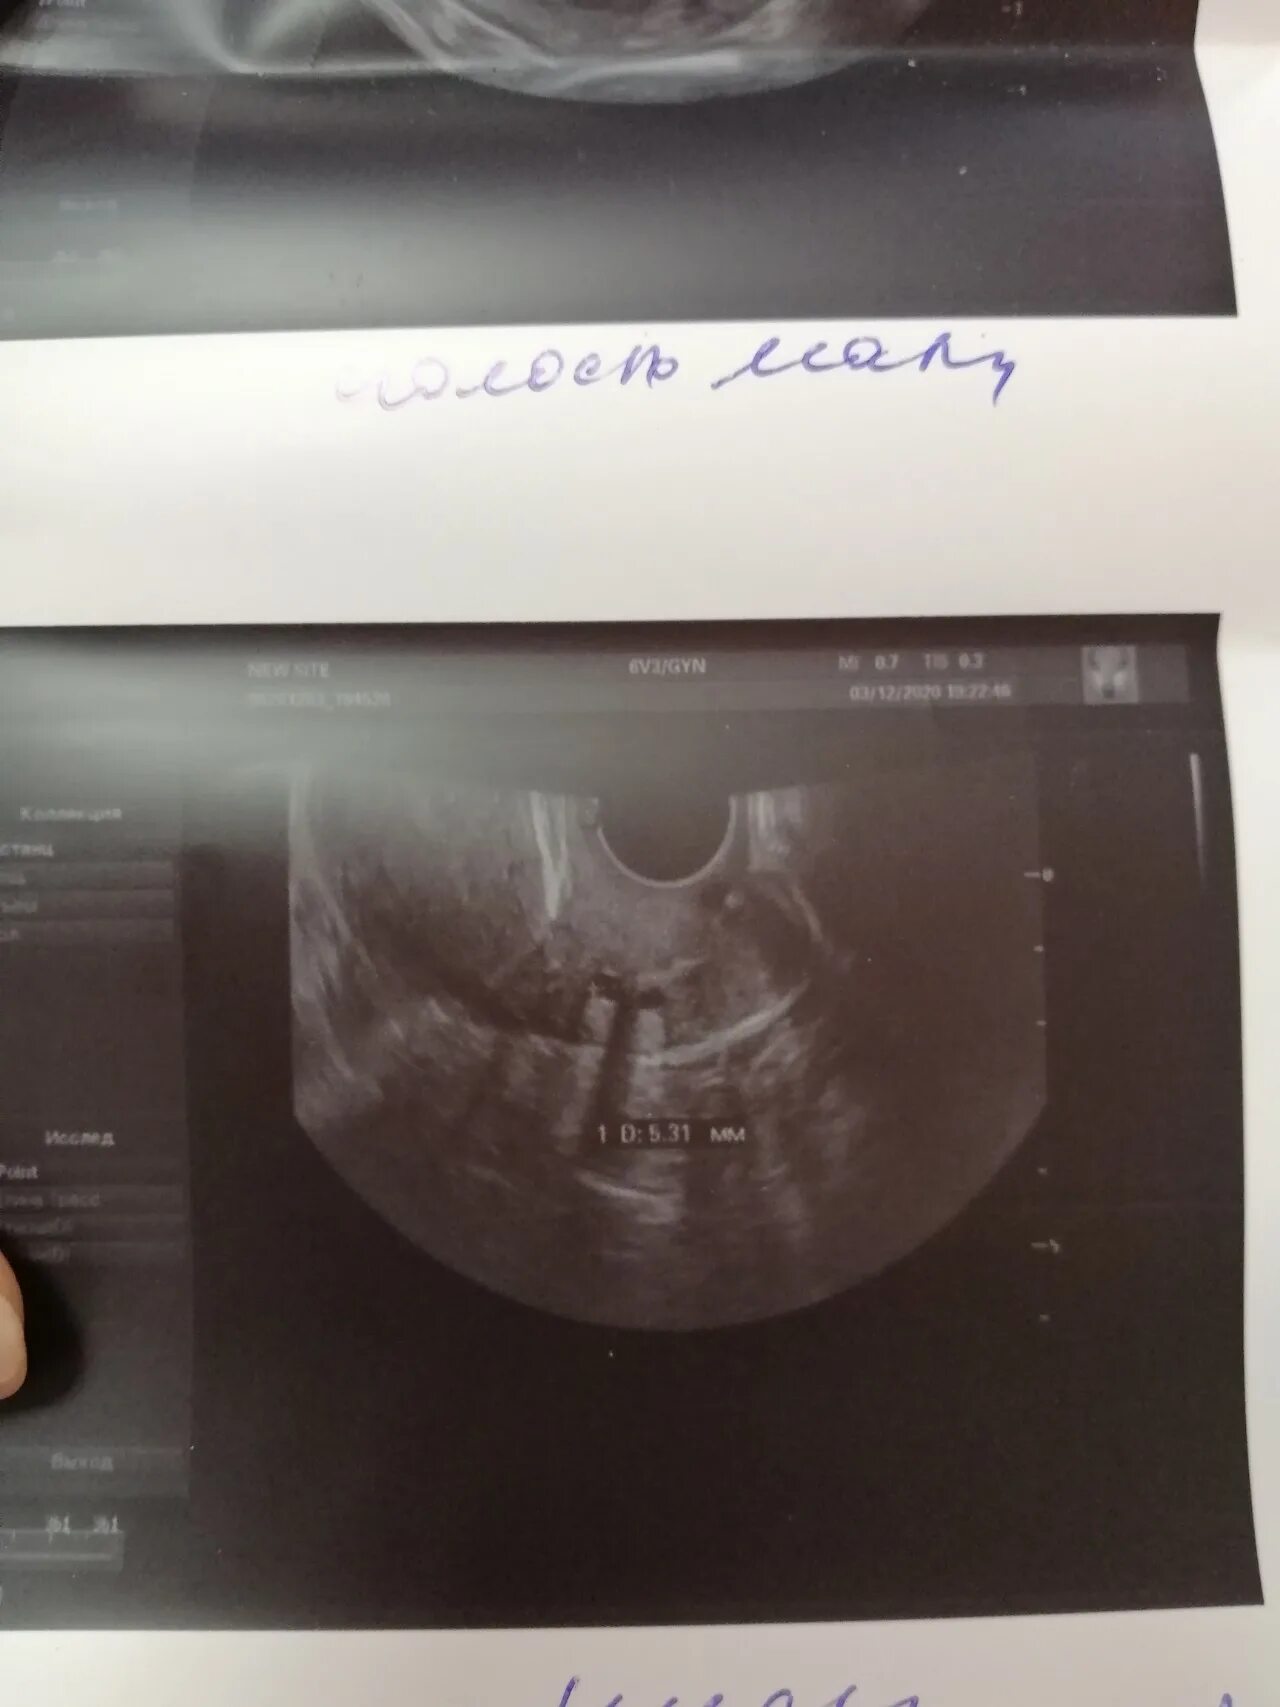

Гематометра симптомы